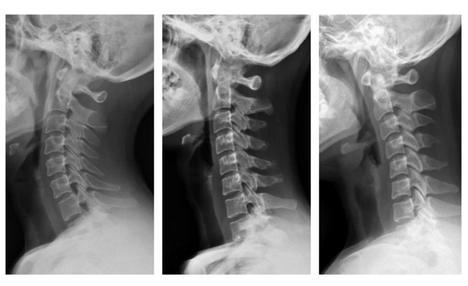

正常生理前凸 颈椎曲度变直 颈椎反曲

人类的颈椎“C”形向前的生理弧线保证了颈椎活动的高度灵活性和稳定性,但人们常常发生违背颈椎生理曲线的姿态和活动,长期伏案工作、学习的人、睡高枕的人,由于头前屈,低头的角度加大,久之,颈椎的生理曲度久会改变,起初是变直,严重时形成反曲(反弓)。颈椎反曲是一种常见颈椎异常表现,是构成颈椎病最常见的病理基础。